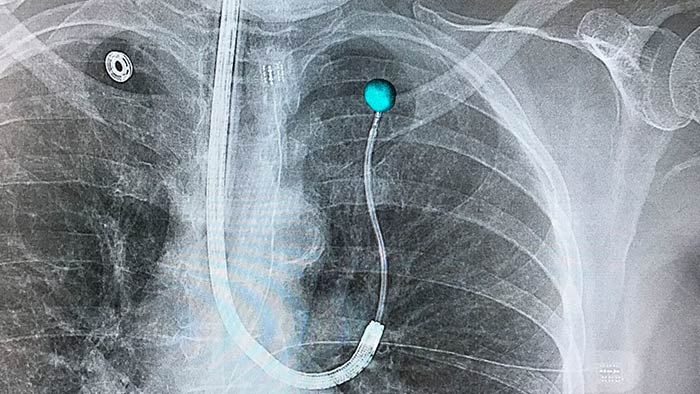

Planning and guidance for percutaneous biopsy, marking and ablative therapy.

with tumor segmentation, 3D navigation support for endobronchial procedures.